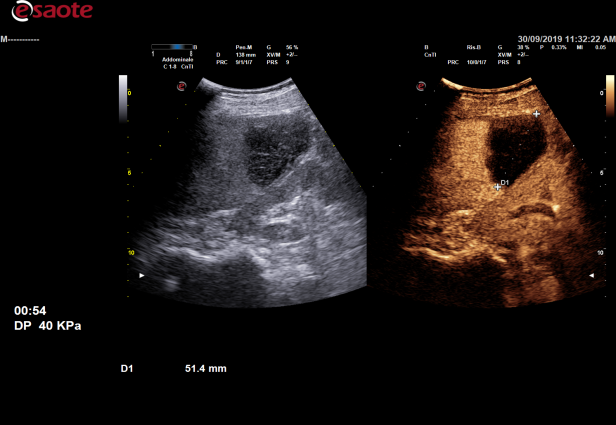

造影谐波成像Ultra-CnTI

通过对发射脉冲频带及能量的精确控制,使脉冲最佳的匹配造影剂微泡的非线性响应,从而获得纯净、丰富的、超强的造影剂回波信号:HFRI 高帧频动脉关注成像-更好的造影动脉相CCPI编码造影成像-利用编码成像原理进行发射和接,提高深部组织的造影穿透力DCTI造影三频段接收技术-提高造影剂检测灵敏度,更少的造影剂用量DP声压精控技术-可最大限度的保护微泡,减少微泡破裂,保证持续的、清晰的造影剂灌注观测,可进一步提高对造影微泡敏感的检测,具有更好的造影延迟相全身应用,尤其高频造影更为显著-腹部、高频、心脏、腔内、术中探头均支持造影功能,具有造影双幅动态显示和一键转换调节功能,造影动态图像连续长时间不间断采集;

术前诊断

术后评估